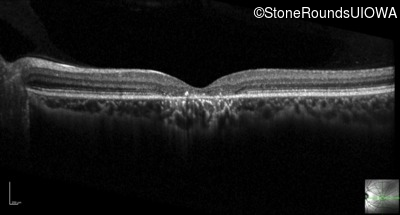

Optical Coherence Tomography - Right - 20/125 -2

Exemplar / OCT Stack

OCT Stack